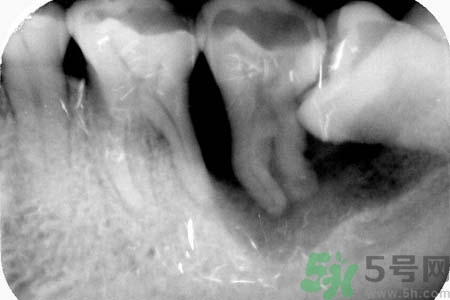

智齒能不拔嗎?智齒長(zhǎng)在大家牙槽的最里面,比較不容易清潔干凈,還容易發(fā)炎。智齒還會(huì)影響人們的臉型,一般去醫(yī)院醫(yī)生都會(huì)建議拔掉智齒。關(guān)于智齒拔了好不好?智齒能不拔嗎?小編為您一一解答。

要不要拔智齒完全取決于大家的智齒長(zhǎng)得怎么樣,事實(shí)上智齒和別的牙沒(méi)有質(zhì)的區(qū)別。只不過(guò)因?yàn)樗奈恢锰厥?,很容易長(zhǎng)歪,而且在功能上又沒(méi)有特別的意義,所以醫(yī)生才建議拔掉。

智齒長(zhǎng)在牙槽最里邊,平時(shí)清潔很難徹底,而且如果長(zhǎng)歪了就更難清潔,所以就特別容易齲壞,慢慢發(fā)展成深齲,甚至感染導(dǎo)致炎癥膿腫等等。拔掉它只是為了絕后患,如果你的智齒長(zhǎng)得好好的,就不要拔掉,畢竟拔牙是有創(chuàng)的手術(shù),會(huì)流血,而且24小時(shí)內(nèi)不能用那一邊吃東西,也挺麻煩的。拔牙一定要去正規(guī)醫(yī)院或診所,因涉及血液,胡亂去小攤可能因不慎感染肝炎或艾滋病。